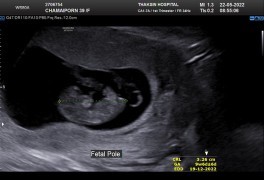

น้องยาวได้ 3.6ซ.ม.

ตอนนี้10wแล้วจ้า

อายุครรภ์ 10w ค่ะ